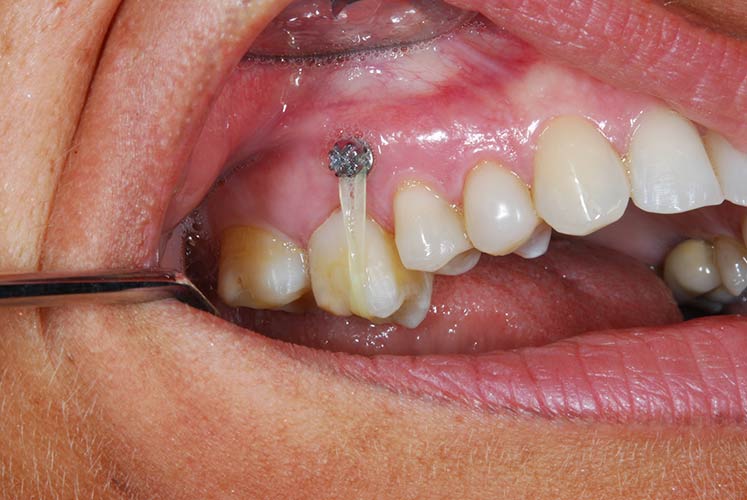

Trattamento ortodontico nell'adulto con intrusione del I° molare superiore mediante l'utilizzo di mini impianti

Trattamento ortodontico nell'adulto